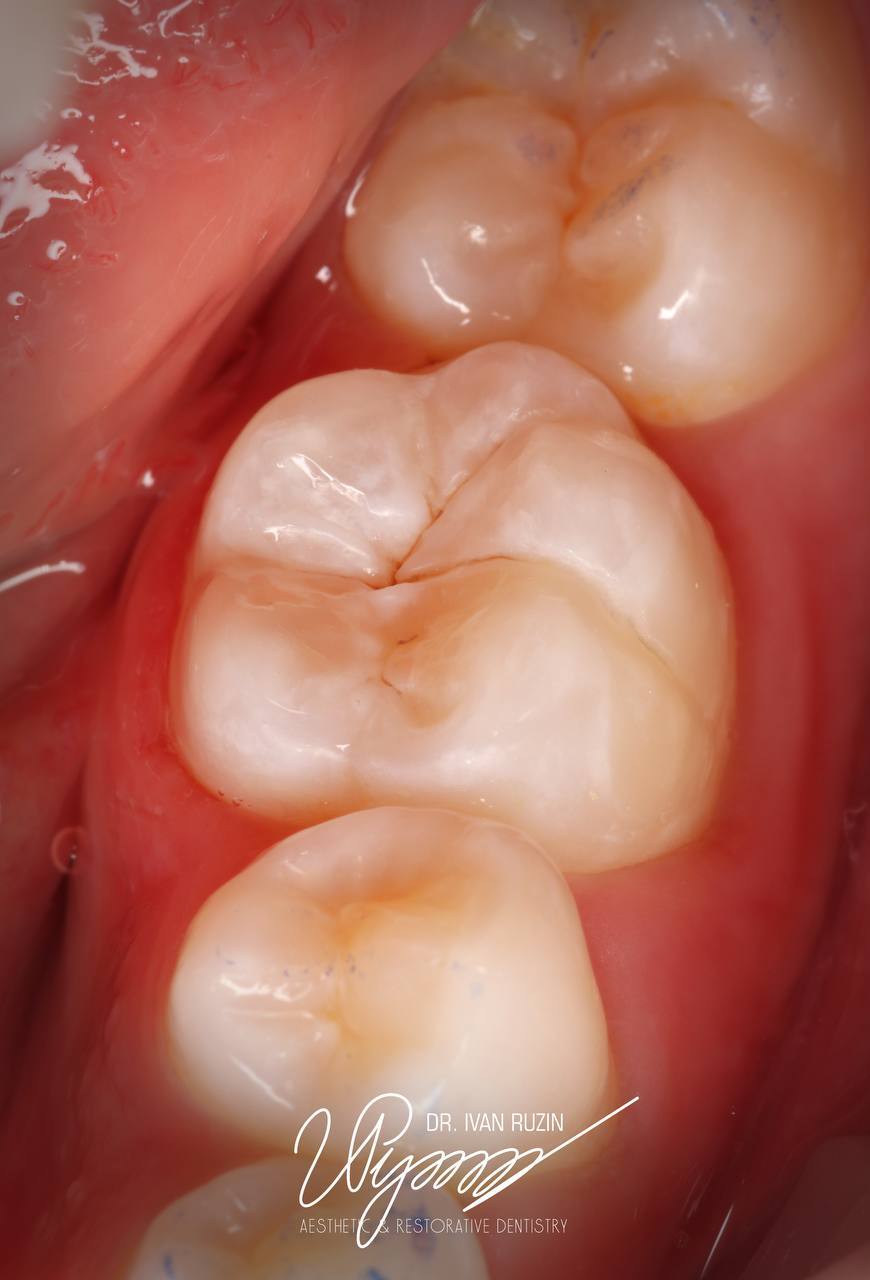

2. Old Filling and Caries Removal (Image 2)